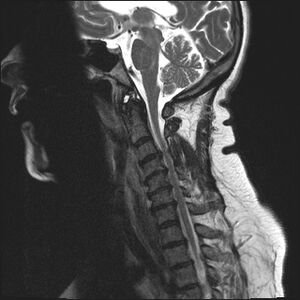

Understanding Cervical Spondylitis

Cervical spondylitis is a degenerative condition affecting the cervical spine (neck region). It occurs due to wear and tear of intervertebral discs, joints, and surrounding structures. Over time, this degeneration can compress nerves and restrict movement.